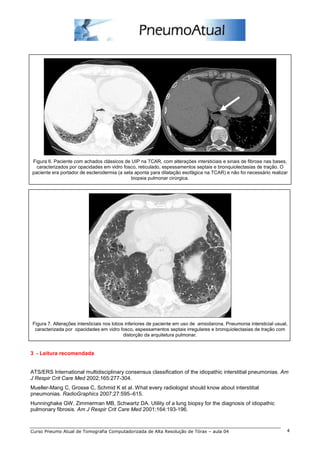

Outros achados de imagem na TCAR de pacientes com UIP são linfonodomegalias hilares e mediastinais

(figura 4). Deve-se também estar atento para detecção de eventuais neoplasias pulmonares (figura 5), já

que estes pacientes têm maior risco de desenvolvimento de carcinomas de pulmão que a população geral.

Figura 4. Linfonodomegalias mediastinais (setas) em

paciente com fibrose pulmonar por UIP. A seta

tracejada demonstra espessamento pleural focal direito.

Figura 5. Paciente com UIP com adenocarcinoma

pulmonar (seta) na TCAR.

A TCAR tem eficácia significativa na avaliação da UIP. Se os achados de imagem forem típicos e a clínica

for condizente com UIP, a hipótese está correta em mais de 90% dos casos, podendo-se eventualmente

dispensar a biópsia pulmonar cirúrgica (figuras 6 e 7). Caso o aspecto de imagem não seja típico na TCAR,

o método pode ainda auxiliar nos diagnósticos diferenciais, tais como sarcoidose, pneumonia por

hipersensibilidade e pneumonia intersticial não específica.